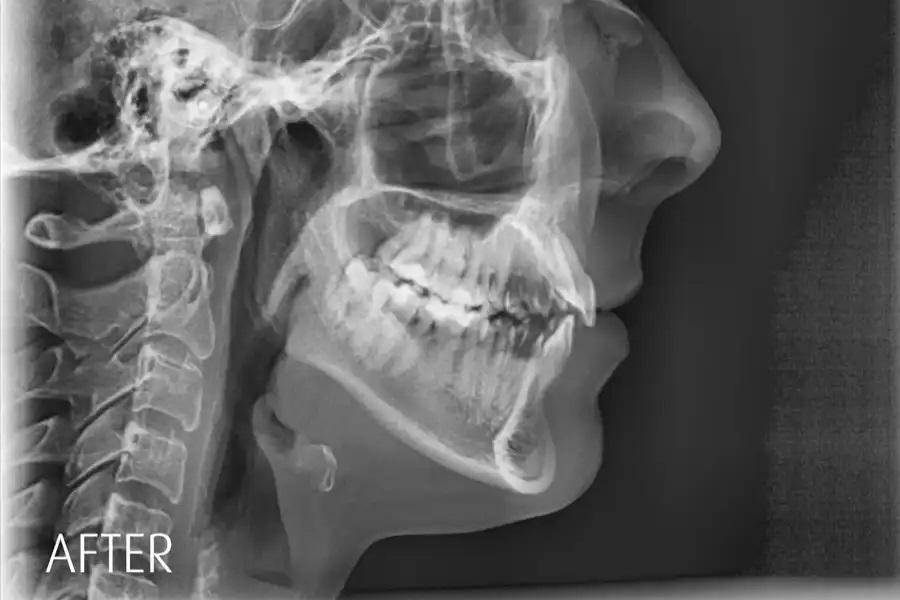

Повторная оценка по данным панорамной рентгенографии и цефалометрии используется для подтверждения интрузии боковых зубов без резорбции корней или изменений в области пазух, улучшения наклона верхних резцов в пределах костной ткани, изменений профиля губ, соответствующих авторотации пр. ч. с., и благоприятных скелетных параметров. (фото 17 – 20)

Фото 19. Цефалометрическая рентгенограмма до лечения. Базовая латеральная телерентгенограмма, демонстрирующая исходные скелетные и зубные соотношения. Верхнечелюстная плоскость и окклюзионная кривая имели выраженный наклон, с акцентированной кривой Шпее, тенденцией к открытому прикусу и уменьшенными значениями вертикального и сагиттального перекрытия.

Фото 20. Цефалометрическая рентгенограмма через 15 месяцев после завершения лечения. Цефалометрический анализ продемонстрировал выраженное улучшение скелетных и зубных параметров. Верхнечелюстная плоскость приобрела более благоприятный наклон с выравниванием окклюзионной кривизны. Отчетливо определяется ротация нижней челюсти пр. ч. с., что привело к формированию положительного вертикального перекрытия, физиологического сагиттального перекрытия и более гармоничного профиля лица. Углы SNB и ANB нормализовались, что соответствует улучшению сагиттального баланса и общей лицевой гармонии.